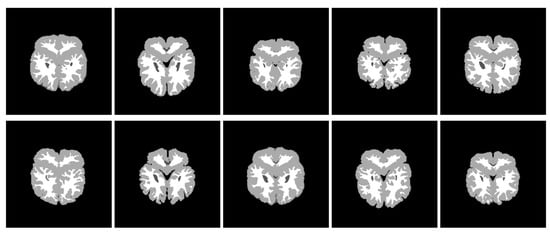

In this section, we show the performance of thresholding segmentation with the convex combination of pseudo grouping functions and the convex combination of grouping functions on 10 T1 weighted MRI images (see Figure 11). The MR cerebrum information as well as hand-operated segmentations originated from the morphometric analysis center of Massachusetts General Hospital. We evaluated the quality of excision by comparing with the ideal manually segmented images obtained on the same web page (see Figure 12). The purpose of this image segmentation was to divide each pixel in the cerebrum into two kinds—gray matter and white matter. In fact, it is a part of brain region volume analysis, which plays a great role in assessing the development of illness, for instance, Alzheimer’s disease, epilepsy or schizophrenia ([39,40]).

Through the convex combination of the above grouping functions and pseudo grouping functions, the results of threshold segmentations of 10 graphs are as follows (see Figure 13 and Figure 14).